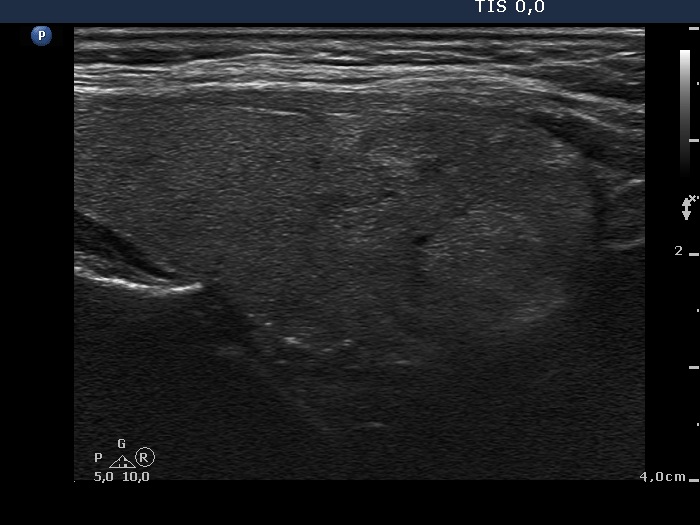

Ultrasonography. The thyroid was echonormal. Both lobes had multiple small discrete lesions, partly echonormal, partly moderately hypoechogenic. There were no nodules of oncological significance.